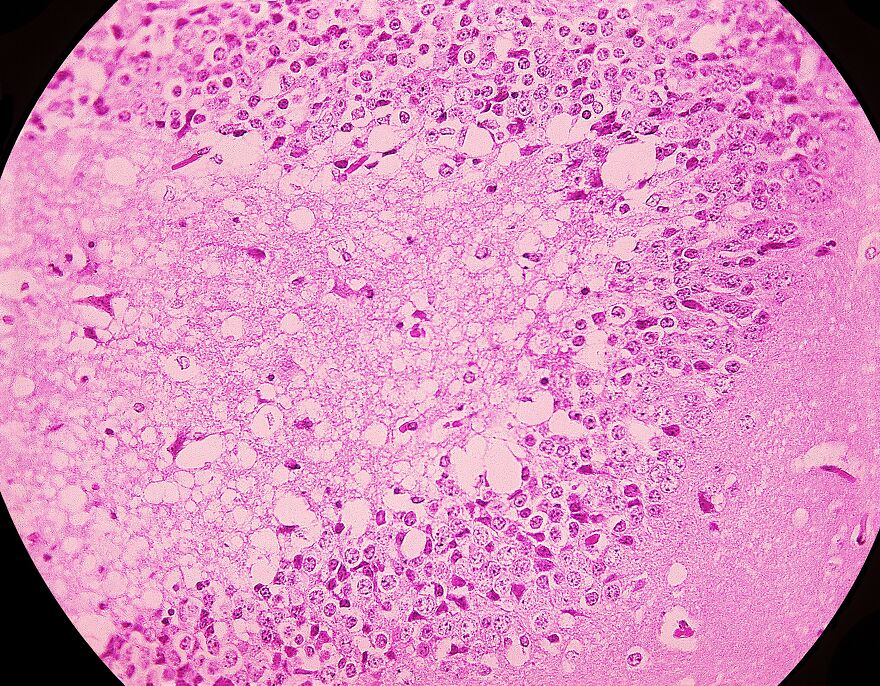

The term “trypophobia skin” refers to the discomfort or disgust people experience when viewing clusters of holes or bumps on human skin. This reaction may be partly due to certain medical conditions that create similar patterns.

Most images shared online under this label are not real medical photos. They are typically digital edits or makeup effects made to exaggerate hole-like textures. Some use lotus pods or other natural textures blended with skin images to provoke a response.

The Dermatology Online Journal explains that while strong feelings of disgust or fear can occur, these reactions are based on perception and disease-avoidance instincts. They are not caused by actual illness.

Since trypophobia is not a recognized skin disorder, the term is often used in online hoaxes and fictional images. These may unfairly stigmatize harmless skin conditions. If you notice any unusual or persistent skin changes, it is important to focus on real symptoms rather than visual discomfort.